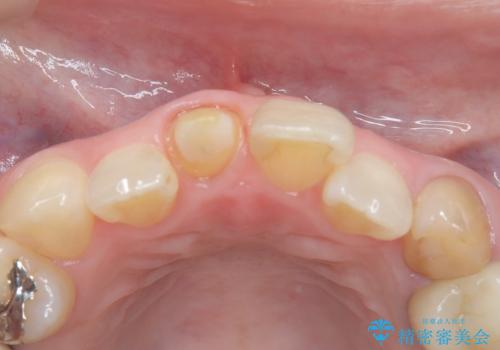

【オールセラミック】前歯の色を変えたい。

- 前歯の色が変色してきたことを主訴に来院されました。

根管治療から被せものまで治療を行いました。

オールセラミックは、透明感があり綺麗な色調を再現できます。